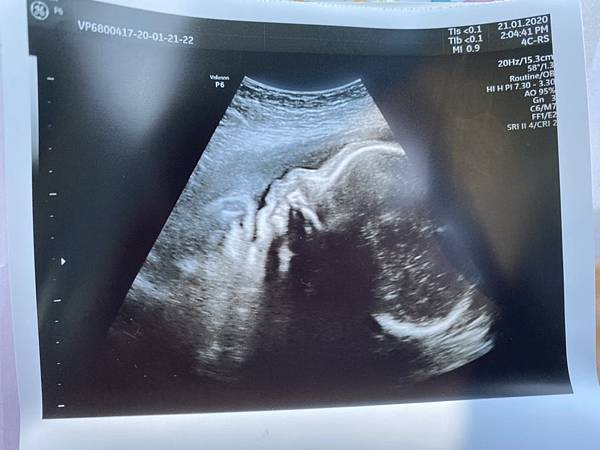

21週開始,不變的還是突發性的呼吸不順暢

每次都會突然好像吸不到氧氣一樣,然後要大口呼吸~

翎Ling 發表在 痞客邦 留言(0) 人氣(308)